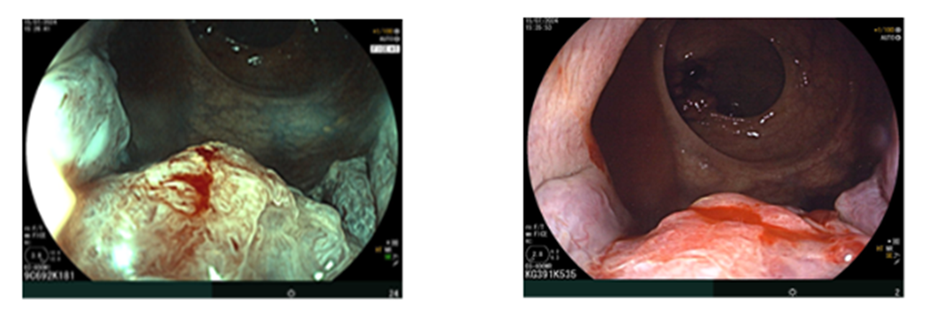

Nội soi đại–trực tràng (07/2024):

Ghi nhận hai tổn thương u sùi ở trực tràng, cách rìa hậu môn khoảng 5 cm và khoảng 10 cm. Tổn thương “phía trong” chiếm gần hết lòng trực tràng; tổn thương “phía ngoài” kích thước khoảng 3,0 cm. Ống hậu môn có đám tổn thương gồ ghề loang lổ.

Hình 1: Tổn thương u sùi ở trực tràng

Hình 2: Tổn thương gồ ghề loang lổ ở ống hậu môn